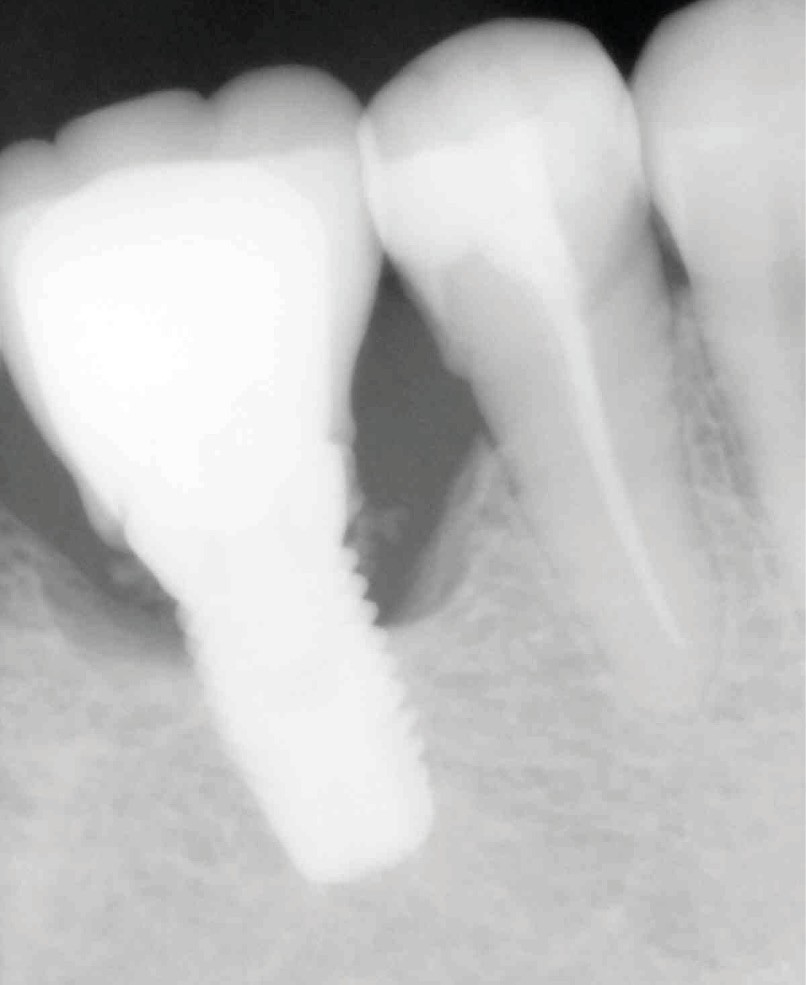

Il est indispensable de faire un contrôle radiographique pour vérifier l’absence de ciment au-delà du joint. Cependant, la radiographie ne permet pas de mettre en évidence les excès vestibulaires ou linguaux, cachés par l’implant ou le pilier.

Cela implique d’utiliser un matériau suffisamment radio-opaque. La littérature préconise sur ce point l’emploi de ciments au carboxylate ou à l’oxyde de zinc. Ils présenteraient la meilleure radio-opacité [3].